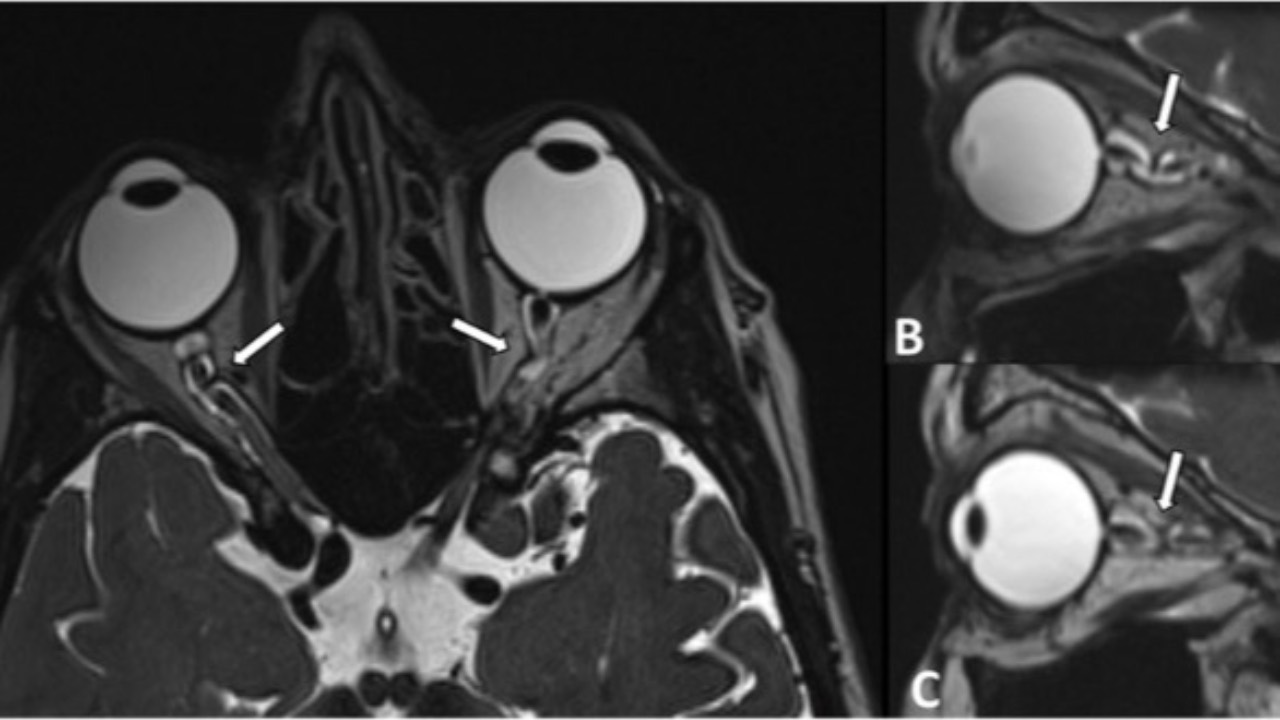

Kinky Normal Tension Glaucoma

Yes, you read that right...

There appears to be a significantly higher incidence of optic nerve kinking in individuals with normal tension glaucoma (NTG) compared to healthy controls. This finding was discovered after retro-bulbar/orbital optic nerve imaging utilizing CT cisternography and MRI in...